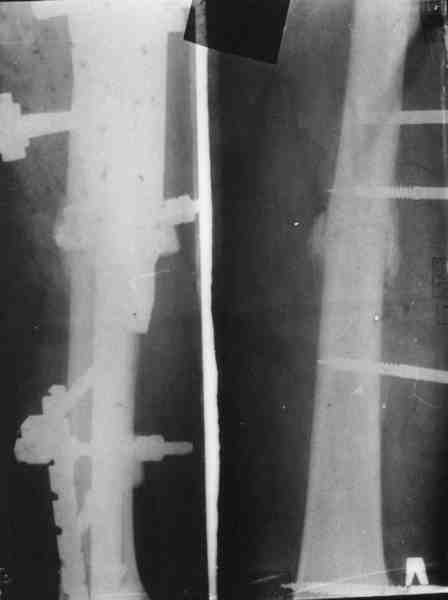

Уважаемый Михаил Викторович! У нас имеется небольшой опыт блокируемых остеосинтезов плечевой кости (20-30), однако был печальный случай (у пациента, в другой клинике, плечо было оперировано гвоздем Кюнчера!!! - произошло отвисание дист фрагмента) , Нами был ваполнен БИОС (проксимальное блокирование одним винтом), через месяц произошло прорезывание порозной кости и погружение винта под кортикал с образованием диастаза между фрагментами, пришлось найти и извлечь этот винт, немного выбить стержень (не

вскрывая место перелома и не убитрая дистальные блокирующие винты) и выполнить проксимальное блокирование двумя винтами.

Так. как вы планируете пациенту повторное вмешательство - может быть удалить прокс. блок. винт забить гвоздь на 10- мм. и сделать блокирование двумя винтами?